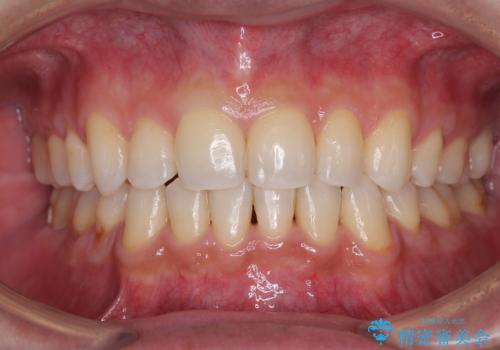

[ マウスピース矯正治療 ] がたつき ねじれのある前歯をきれいにしたい

![[ マウスピース矯正治療 ] がたつき ねじれのある前歯をきれいにしたいの症例 治療前](https://seimitsushinbi.jp/wp/wp-content/uploads/2025/04/8438e7299f1b9566ac213e8e9f7db5f6-500x350.jpg?v=1745226068)

![[ マウスピース矯正治療 ] がたつき ねじれのある前歯をきれいにしたいの症例 治療後](https://seimitsushinbi.jp/wp/wp-content/uploads/2025/04/IMG_0097-500x350.jpg?v=1745225947)